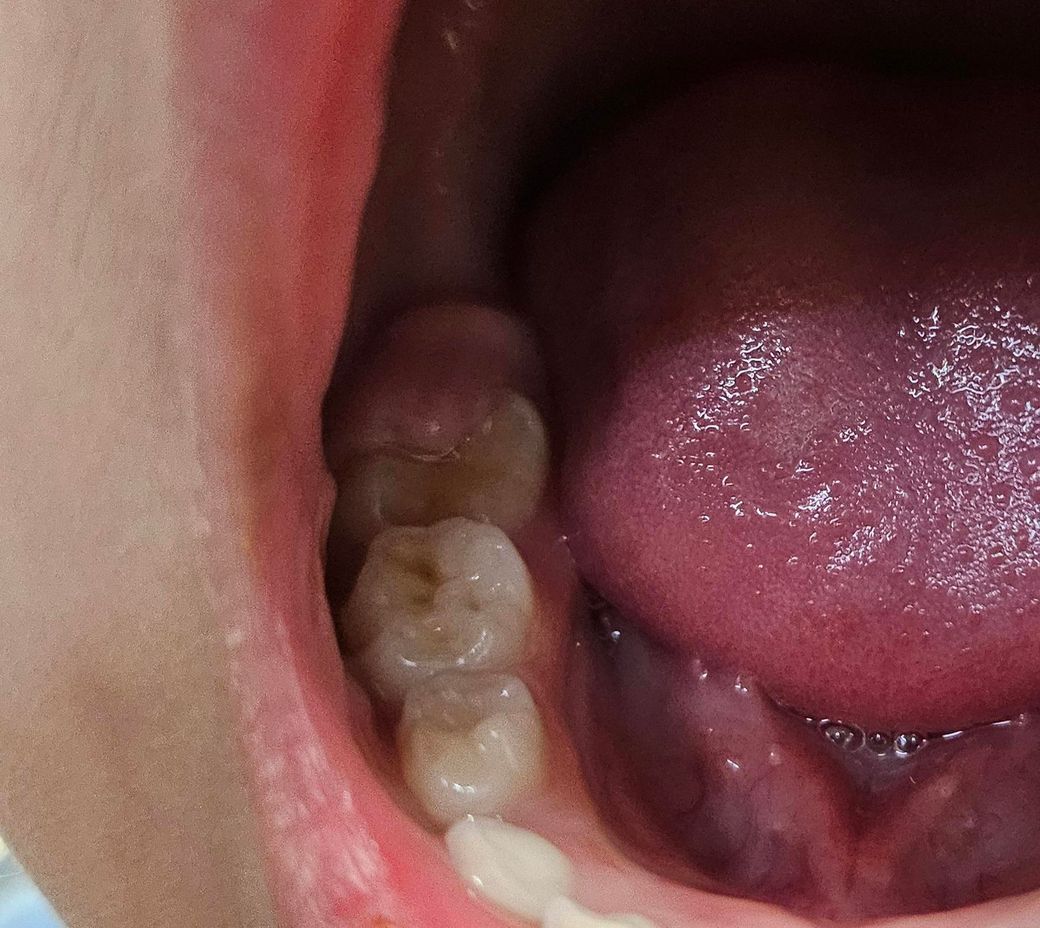

아직 아프다고는 안하는데 이거 왜그런건지 치과를 가봐야되는지 아니면 그냥두면 자연스럽게 괜찮아지는건지 걱정되네요 답변부탁드립니다

사진으로 봤을 경우에는 정상적으로 어금니가 맹출되고 있는 것입니다. 맹출되는 과정에서 부분적으로 맹출된 부분에는 잇몸이 올라와 있을 수 있습니다. 영구치아가 자연적으로 맹출이 되면서 해당 부위는 자연스럽게 없어지게 됩니다.

영구치가 맹출되고 잇는거 같습니다. 유치가 흔들리면 치과에 가셔서 유치를 발치하시면될것같습니다.

영구치가 덜 나온 상태로서 잇몸이 일부 남아있는 것입니다. 영구치가 올라오면 자연스럽게 없어집니다. 밥 씹기 불편하면 치과에서 잇몸 잘라내기도 하지만 대부분 그냥두면 없어집니다.

보통 맹출중인 치아 위로 잇몸이 자라있는 것을 치은판개라고 하며 원활한 치아 맹출, 위생관리를 위해 해당 과증식 부위 절제가 필요할 수 있습니다 치과가보세요